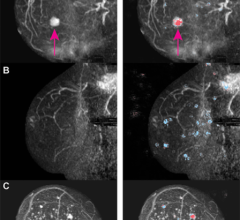

Magnetic resonance imaging (MRI) can be used for breast imaging as an alternative to mammography.

June 6, 2024 — Subsequent rounds of abbreviated breast MRI (AB-MR) screening in patients with dense breasts had lower ...

February 9, 2024 — An innovative breast imaging technique provides high sensitivity for detecting cancer while ...

Breast cancer remains a significant health concern, responsible for more than 600,000 deaths annually. Early detection ...